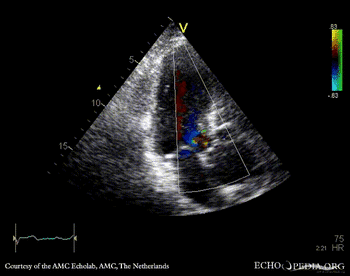

A3CH A3CH with Color Doppler: mild aortic regurgitation